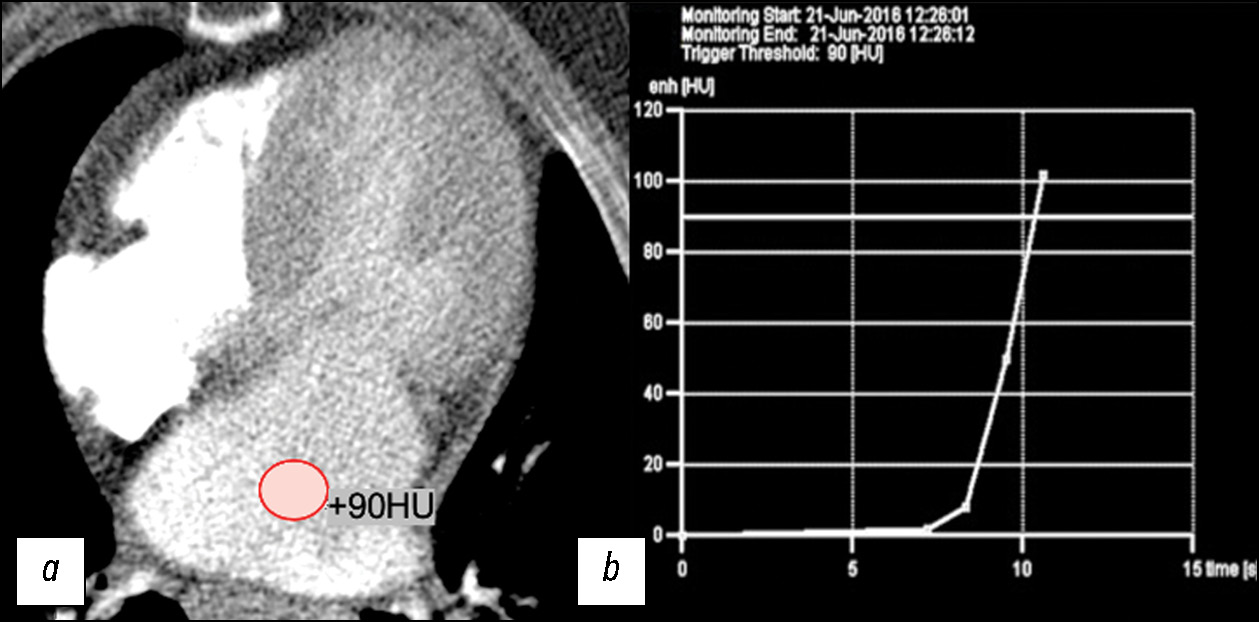

MATERIALS AND METHODS: The retrospective data analysis included 47 patients with hypertrophic cardiomyopathy (mean age, 52±7 full years) before surgical correction. computed tomography was performed using our protocol with automatic bolus tracking in the left atrium with a 90 HU threshold and biphasic contrast injection to assess the heart chambers and coronary arteries anatomy and mitral valve morphology. Moreover, to assess myocardial structure remodeling, iodine dual-energy computed tomography maps obtained with delayed contrast enhancement were analyzed. All patients with hypertrophic cardiomyopathy were classified by morphological types. The anatomy of chordopapillary apparatus was evaluated in each case.